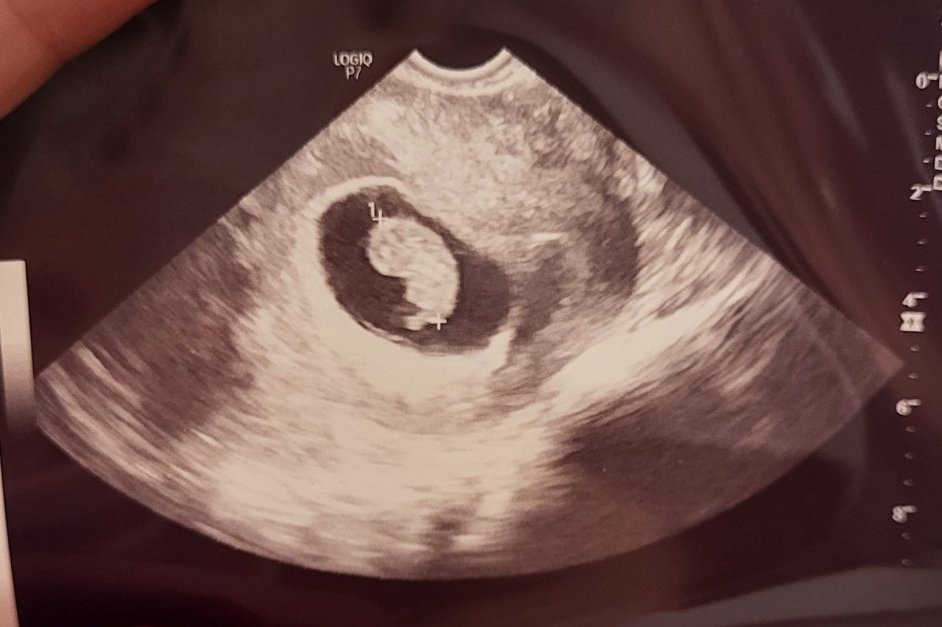

Чета ви, но нямам време да се включа . Ходя напред назад като простинал кон . Онзи ден се разделихме с Персенска, стана ми малко тъжно ,бях свикнала при нея . Каза ми да се ориентирам вече към АГ, който да ми води ЖК и аз преди това си бях избрала Терзийска в Благоевград. Много внимателна и организирана ,имам и доверие. На прегледа при Персенска бебчето излезе 8+5 (аз бях 8+6) ,гледа ме с вагинален ехограф . На следващият ден при Терзийска излезе 8+3 (вече бях в 9+0) , но тя ме гледа с коремен ехограф . Дали тази разлика идва от различните ехографи ?

Ето го малкото вече оформящо се човече!